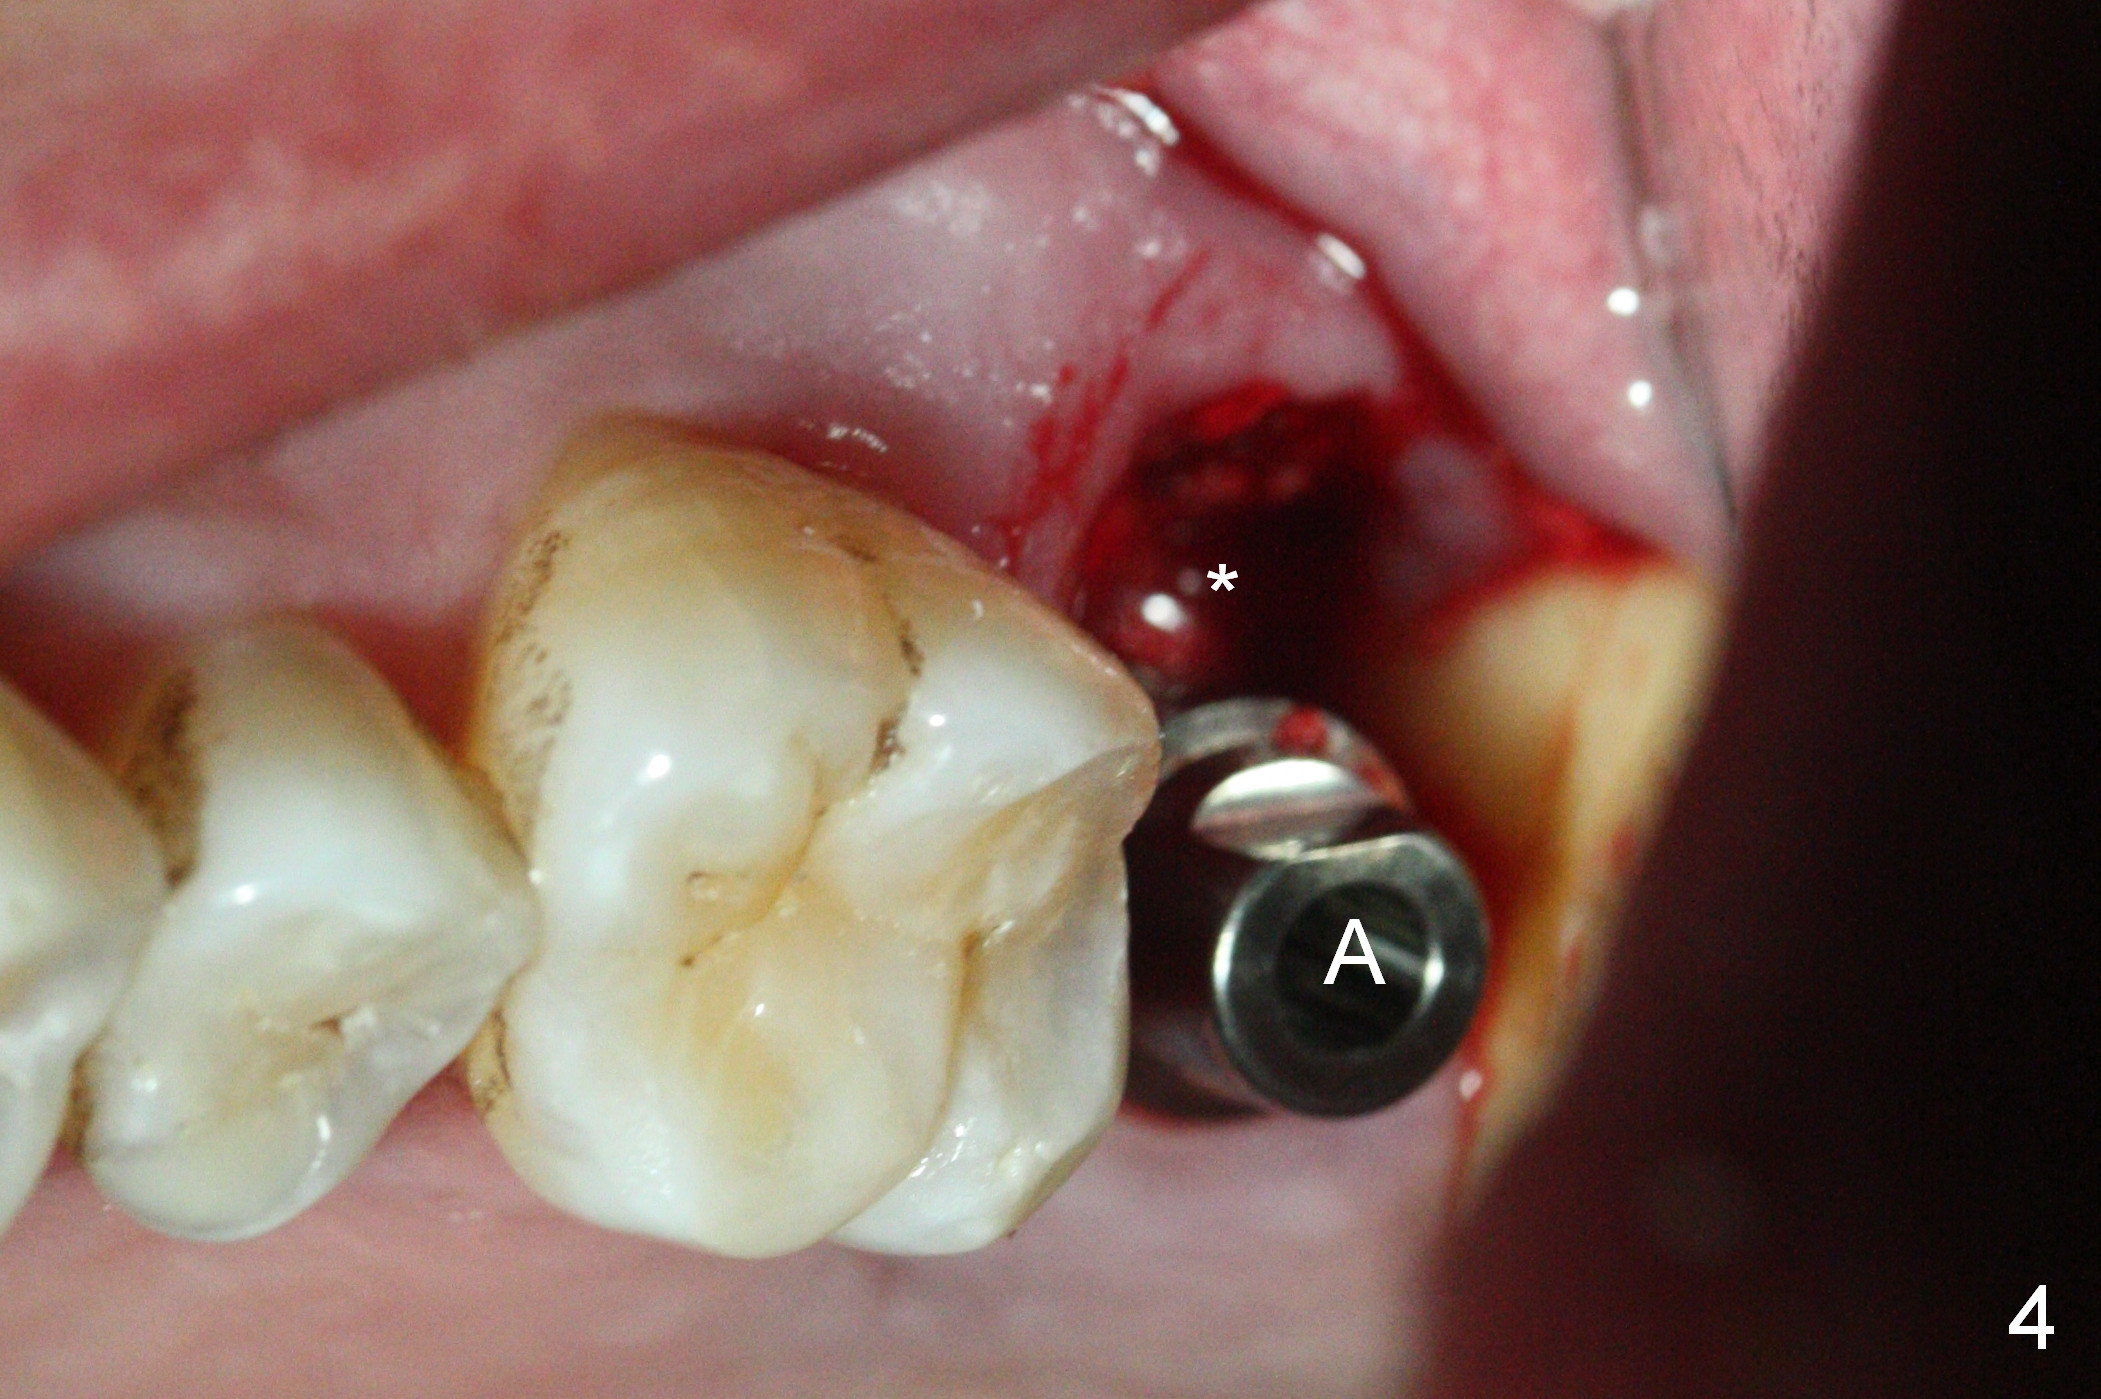

When the tooth #15 is extracted, the buccal plate is found to have been lost. The depth of osteotomy in the native bone is 8.5 mm (Fig.1,2). When a 5.5x15 mm implant is placed (Fig.3), the insertion torque is > 55 Ncm. The implant is palatally placed with a 10x10 mm Osteogen plug being placed in the deep portion of the buccal gap for buccal plate repair (Fig.4 *). The superficial portion of the remaining socket is filled with .5-1.5 mm allograft/autogenous bone/Osteogen (Fig.5 *). The drawback of this procedure is that the abutment is placed prior to placement of the graft. The latter fails to reach the deepest area of the defect. If periimplantitis develops because of insufficient graft, do it again in due time.